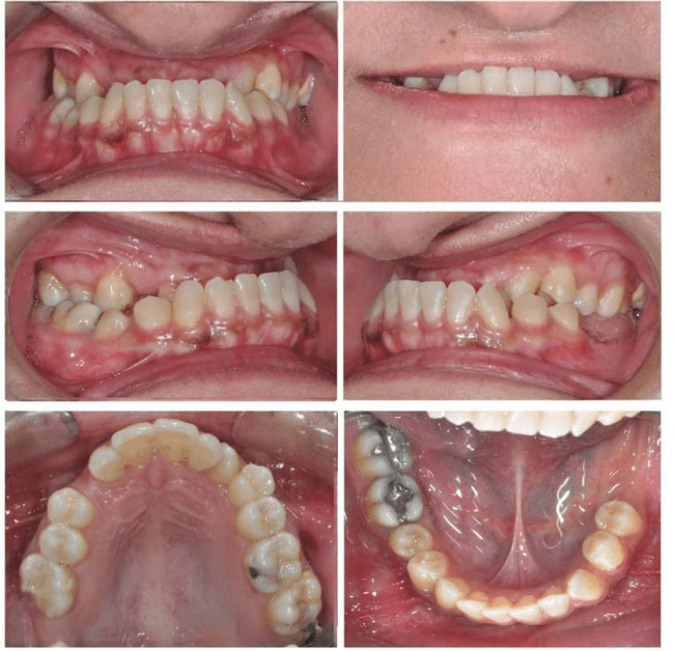

The surgery-first approach (SFA) is gaining popularity in orthognathic surgery because it makes treatment duration shorter and more satisfying for patients. However, its effectiveness in complex cases isn't fully understood. Here, we describe a rare case where SFA was used to fix problems caused by missing posterior teeth and a deep bite, which made traditional pre-surgery orthodontic treatment impractical. A 34-year-old woman had facial asymmetry, bite issues, and trouble chewing due to a misaligned jaw. X-rays showed the problem, confirming that orthognathic surgery was needed. Planning for the surgery involved moving the upper jaw forward and the lower jaw backward, using specific bone-cutting techniques. The surgery, done with the patient under general anesthesia, went well. Orthodontic brackets were added during surgery which was aided by an orthodontist to make follow-up orthodontic treatment easier. The patient recovered uneventfully and saw improvements in how her face looked, how her teeth fit together, and how well she could chew. Later, more orthodontic work fine-tuned her bite, making sure the changes lasted and kept her satisfied. This case shows how combining orthodontics with the surgery-first method can be successful in orthognathic surgery. It brings benefits like shorter treatment times and immediate improvements in appearance. Our results match other recent studies that also found good outcomes with the surgery-first approach and quicker recovery times. While more research is needed, our case adds to the evidence that SFA can lead to successful orthognathic surgery results.